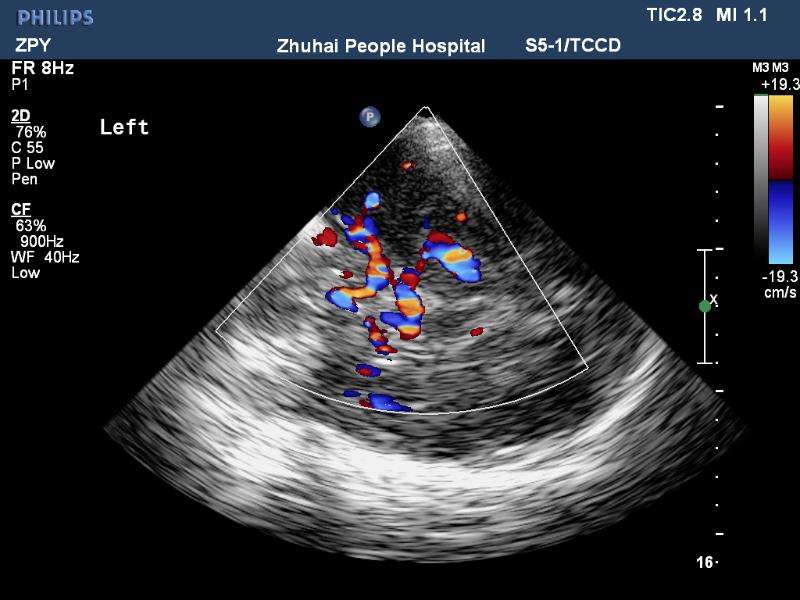

經顱彩色編碼雙功能超聲(transcranial color-coded duplex sonography

TCCD)是一種非侵入性發現顱內動脈異常血流動力學狀態的可靠方式。TCCD成像原理是在TCD基礎上增加了二維灰階實時顯像以及彩色編碼雙功能超聲成像,在二維顯示顱內解剖結構的同時,同時對運動紅細胞產生的多普勒頻移進行彩色編碼。應用TCCD檢測時可以通過在感興趣區內多點取樣,得出取樣容積內多普勒頻移曲線,通過雙側對比、左右對比以及前后對比,綜合評價缺血性腦血管病受檢者Willis環的血流動力學變化。